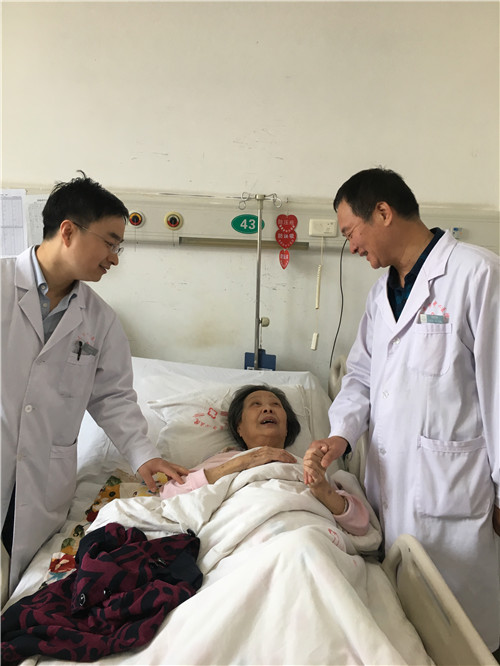

患者伤口愈合良好

“太感谢翁主任和骨一科的医生们了,你们又一次的治好了我的病。”老人说道。

“你们的信任,是我们最大的动力。”翁主任握着老人手说道。